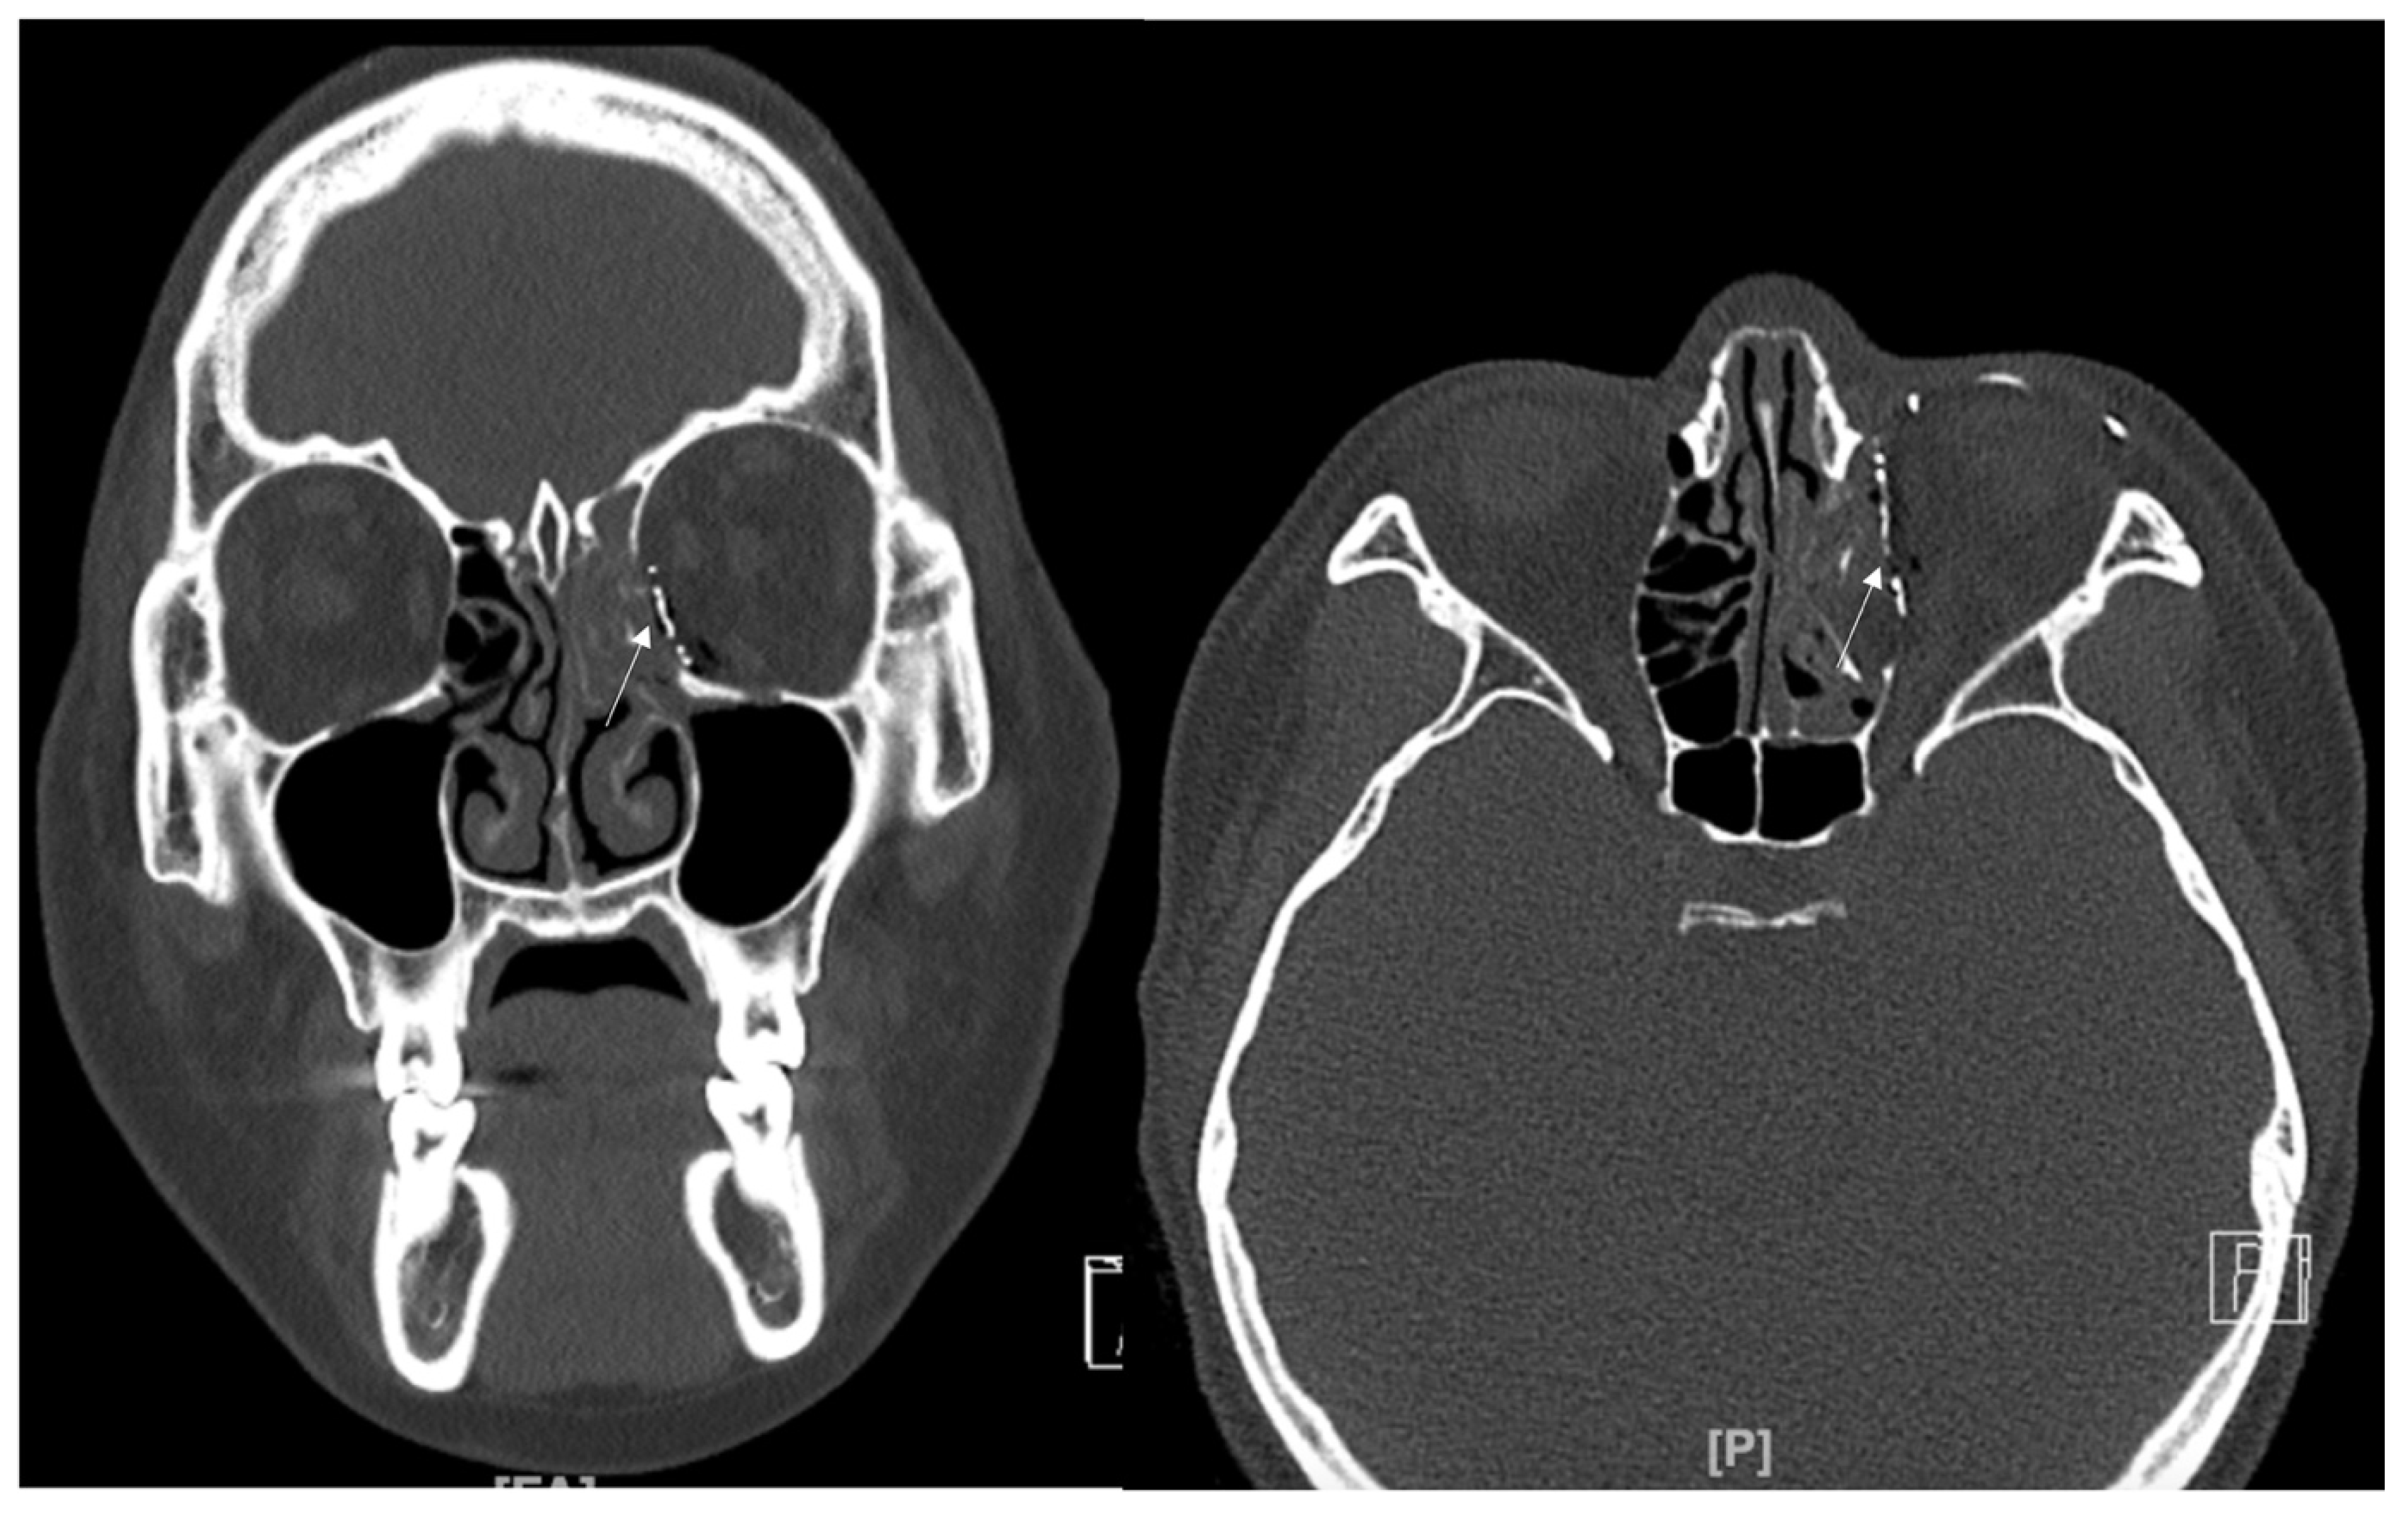

A 34-year-old female patient came to our clinic with left eyeball swelling and ecchymosis caused by a direct trauma to the eyeball. The patient complained of pain and discomfort with eyeball movement (Figure 5). We surgically approached the medial orbital wall fracture two days after the accident. After the subciliary incision, the fracture was exposed. The titanium-reinforced porous polyethylene (TR-PPE) plate was placed on the fracture site using a single screw at the inferior orbital rim (Figure 6). The patient was discharged on postoperative day 2 with significantly improved pain and discomfort.

Figure 5. Case 3. Preoperative facial CT scan (coronal and axial view) of the 34-year-old female patient with left medial orbital wall fracture (white arrow). The fracture sites were designated with white arrows.

Figure 6. Case 3. Follow-up facial CT finding (coronal and axial view) of the same patient. The titanium-reinforced porous polyethylene (TR-PPE) plate was placed on the inferomedial orbital wall using a single screw at the inferior orbital rim. (White arrow).